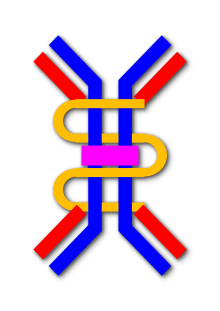

In secretory IgA, the form found in secretions, polymers of 2-4 IgA monomers are linked by two additional chains; as such, the molecular weight of slgA is 385,000D. One of these is the J chain (joining chain), which is a polypeptide of molecular mass 15kD, rich with cysteine and structurally completely different from other immunoglobulin chains. This chain is formed in the IgA-secreting cells.

The oligomeric forms of IgA in the external (mucosal) secretions also contain a polypeptide of a much larger molecular mass (70 kD) called the secretory component that is produced by epithelial cells. This molecule originates from the poly-Ig receptor (130 kD) that is responsible for the uptake and transcellular transport of oligomeric (but not monomeric) IgA across the epithelial cells and into secretions such as tears, saliva, sweat and gut fluid.